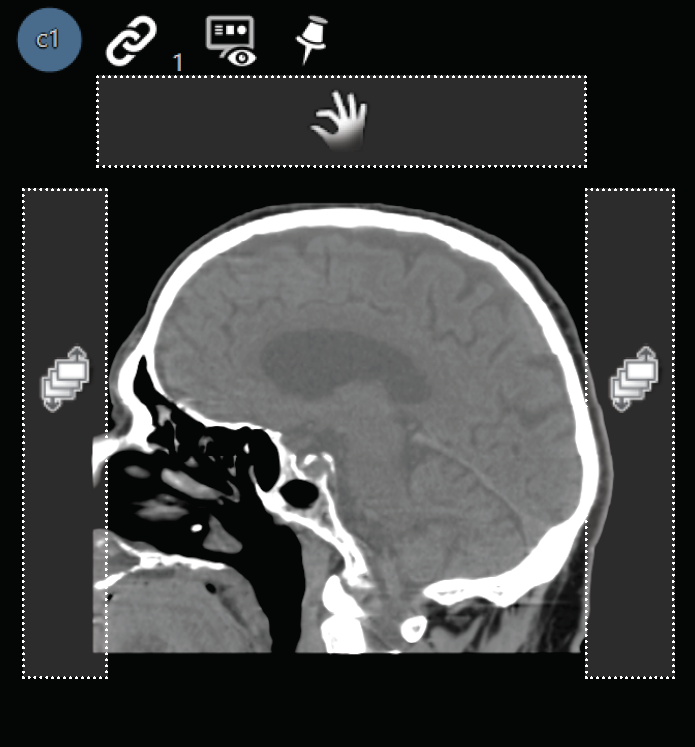

Image Frame Information

Images are shown with a (c) plus a number for current images or a (p) plus a number for priors. These indicators are located in the top left corner of the image frame.

PACS Desktop Viewer

Images are shown with a (c) plus a number for current images or a (p) plus a number for priors. These indicators are located in the top left corner of the image frame.